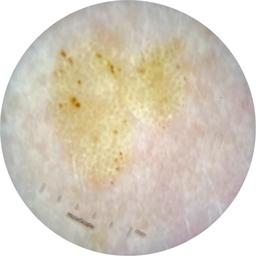

MEL-SELF - Dermoscopic

- Name: MEL-SELF - Dermoscopic

- Number of images: 3,008

- Number of specified lesions: 837

- Number of specified patients: 246

Dermoscopic lesion images (close-up views of benign and malignant lesions) from the MEL-SELF trial (the Melanoma Self Surveillance trial).